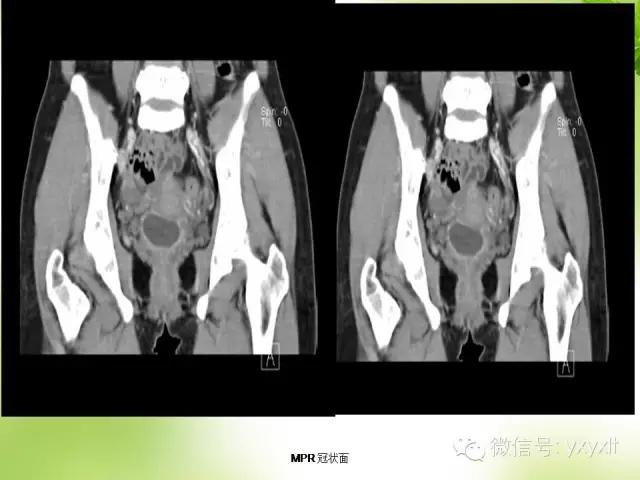

术中:膀胱后方宫颈前方约4.0cm×3.0cm的囊性肿块,子宫双附件无异常。切开膀胱与子宫间腹膜,在此间隙至囊性包膜,在包膜外分离囊肿,游离至宫颈处见囊肿与宫颈及阴道穹窿粘连紧密无法分开,连同部分阴道后壁及宫颈完整切除囊肿。

肉眼所见:囊肿大小约4.0cm×3.0cm×3.0cm,切开后流出清亮液体约30ml,包膜完整光滑,内壁光滑。(盆腔肿块)囊肿,多考虑副中肾囊肿。

CT:囊肿表现为单房或多房的薄壁水样低密度病灶薄壁囊性肿块,边缘清楚光整。增强扫描未见强化。